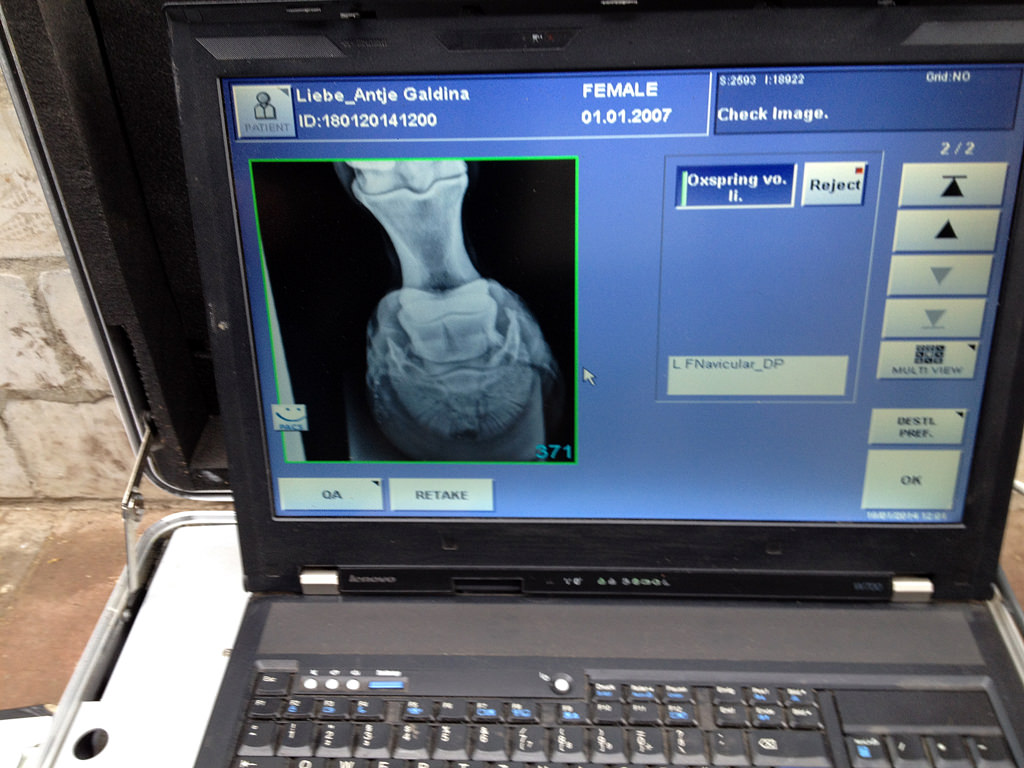

Heute war es sehr anstrengend für Galdina. Neben dem Hufschmiedtermin war auch noch mein Tierarzt da – zum Impfen, zum Röntgen des linken Vorderhufs und zur Kontrolle der Zähne. Zunächst hat Markus wieder eine Pediküre gemacht. 😉 Bevor die Eisen vorn aufgenagelt wurden, wurde der Huf geröngt. In der Seitenansicht waren soweit keine Auffälligkeiten, aber bei der Aufnahme von vorn wurde eine Veränderung sichtbar. Aussage meines Tierarztes:

Galdina und ich – bereit zum Röntgen